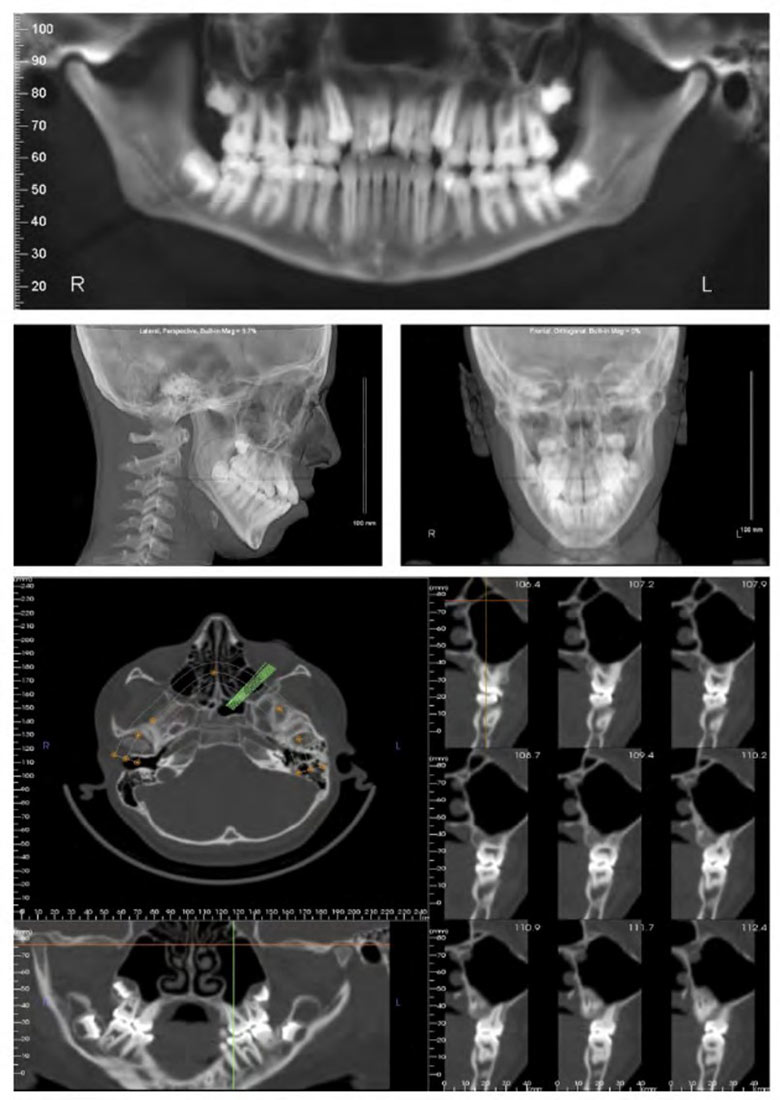

Der Kieferorthopäde kann feststellen, ob und wann die Entfernung der Weisheitszähne notwendig ist. Dazu muss eventuell während der Stabilisationsphase noch ein Panoramaröntgenbild angefertigt werden und die Entfernung der Zähne mit dem Hauszahnarzt oder Kieferchirurgen besprochen werden.